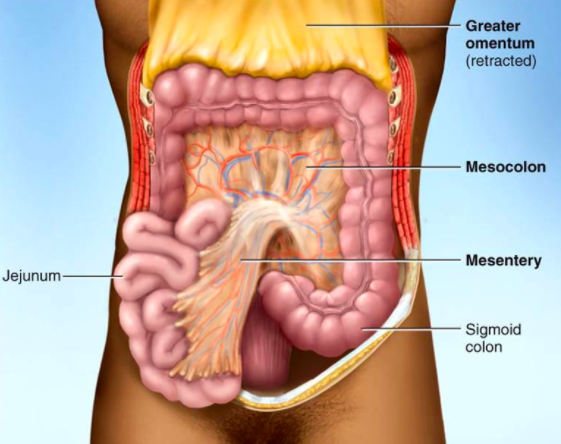

▼腸系膜:早在1508年就被達文西發現的器官,可是大家都對它很不了解,早起科學家甚至認為這只是破碎的組織,不過它卻能夠引導血管和神經前往身體內正確的位置,直到2017年才正式被確認為器官。